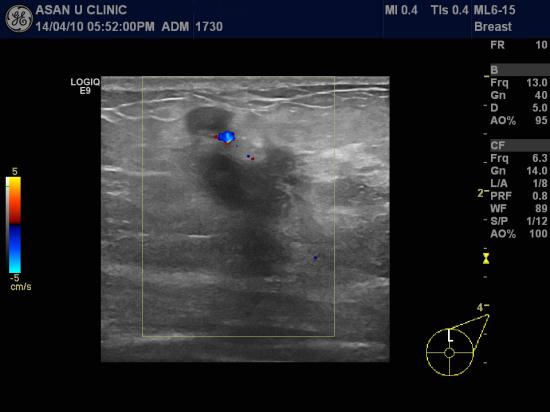

아산유외과 개원 후 86번째 유방암진단.

좌측유방에 몽울이 만져져 내원하신 67세 여성분입니다.

좌측 액와부에도 림프절비대가 있어

유방초음파를 통해 병변확인하고 중심핵생검과 세침흡인검사로

유방종괴와 액와림프절을 검사하였고

각각 유방의 침윤성 유관암 및 겨드랑이 림프절의 암전이 확인하였습니다.

주로 발병하는 나이는 아니지만

60대에도 유방암은 방심할 수 없습니다.